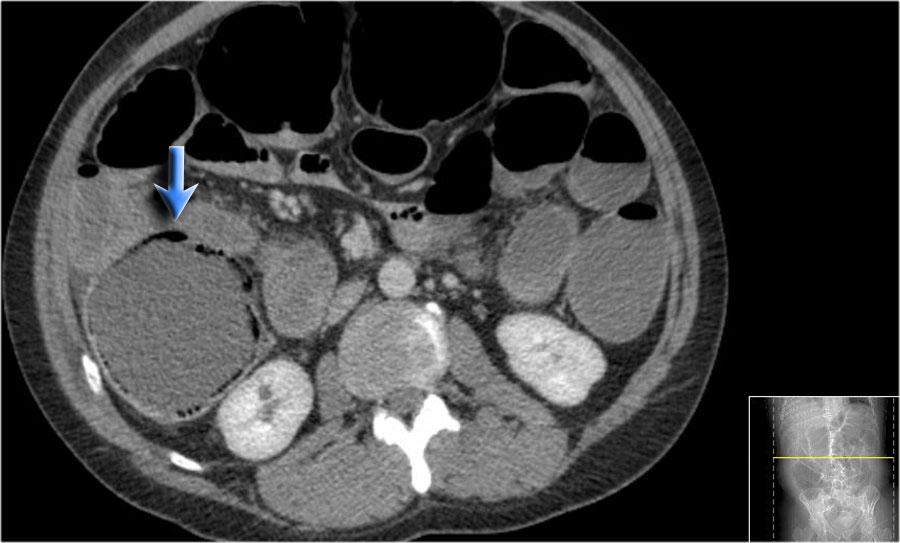

Đây là bệnh nhân có khí thành ruột ở manh tràng và đại tràng lên do tắc nghẽn bởi ung thư đại tràng sigma (mũi tên).

Khí trong thành ruột cho thấy nguy cơ thủng ruột sắp xảy ra.

Đây là một bệnh nhân khác có khí thành ruột do tắc nghẽn.

Sau khi giải áp, thành manh tràng trở về bình thường.